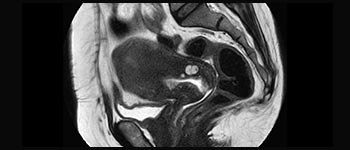

La Sra. Silvia Schiffer, directora y radióloga experta en la clínica Radiologie Schiffer, en Alemania, comparte sus experiencias con el sistema de RM Prodiva 1.5T.

Mayor fiabilidad diagnóstica en neurooncología